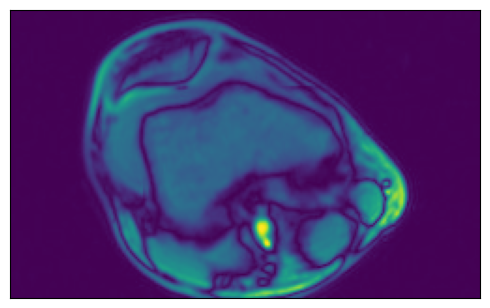

[8]:

print(f"Sample shape: {tensor_3d.shape}")

plot_tensors(

tensor_3d[0, :, :],

tensor_3d[1, :, :],

tensor_3d[2, :, :],

tensor_3d[3, :, :],

)

Sample shape: (5, 512, 512)

../../../../_images/examples_general_data_loading_numpy_reader_dynamic_mode_16_1.png

Region-of-interest (ROI) API#

In the example shown above, we see that the relevant data is concentrated in the upper left quadrant of the image and the rest does not contain useful information. This is not true for all the images in the dataset, but it will serve us as a good example to demonstrate ROI reading.